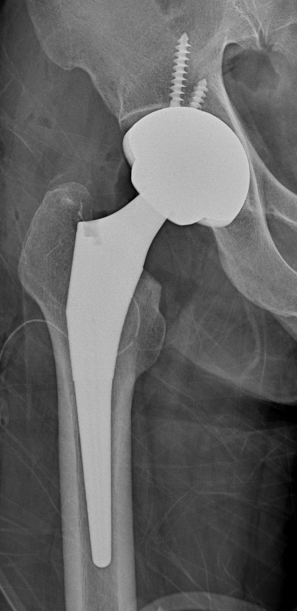

- THRA는 비구와 대퇴골두 모두를 인공관절로 치환하는 수술로, 관절 전체를 교체하는 방식이다

대퇴골두를 제거하고 금속 대퇴 주대(Stem)를 대퇴 골수강에 시멘트로 충전하거나 시멘트 없이 단단히 끼워넣어 고정한다.

대퇴 주대 상단에 금속 또는 세라믹형 볼을 끼워 대퇴골두를 대신하게 하며, 손상받은 비구 관절연골을 제거하고 금속 소켓인 비구컵을 비구에 끼어 넣는다. 때로는 금속나사를 이용하여 비구컵을 고정하기도 한다.